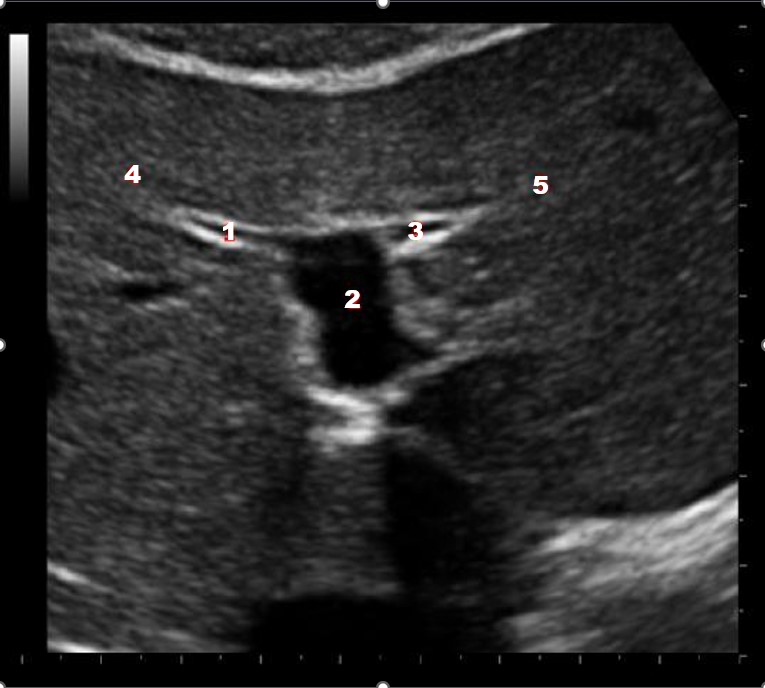

What structure/vessel is indicated by #3?

Gastroduodenal artery

What structure/vessel is indicated by #2?

Head of pancreas

During an abdominal ultrasound, a 4 mm circular anechoic structure is identified at the posterior portion of the pancreas head. Color flow is not identified in the structure. What is it?

Common bile duct

Which of the following structures is labeled #2?